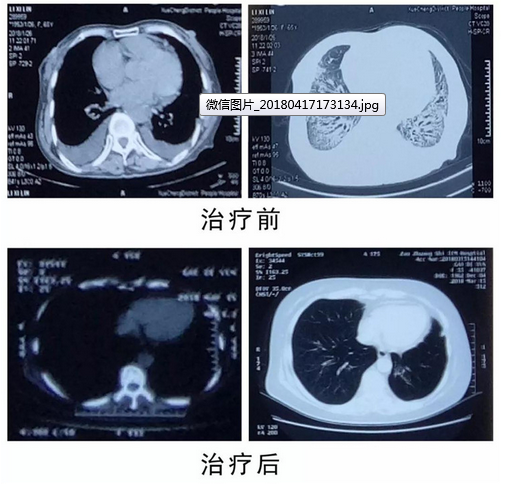

2月21日,患者因“双前臂皮肤僵硬,伴心慌胸闷喘憋”来我院就诊,经过系统诊察,诊为“系统性硬皮症、心功能衰竭、肺间质纤维化”收入我科住院诊治。该患者是我们的老患者,最初也是我们给确诊的多系统硬皮症,长期随访病情基本平稳。本次病情恶化,加之外院拒收,让患者及家属一度陷入困境,放弃不甘心,救治无路求医,带着担忧和治治看的心态再次来到我院,我们全体医护人员迎着挑战开始了二十余天的精心救治。起初患者病情呈日渐加重趋势,患者及家属不甚理解,经多次与患者家属沟通,分析患者原发病对心、肺等全身重要脏器的影响,将时时危及生命,慢慢得到了患者及家属的理解和配合。住院期间,通过三级医师查房认真询问病情及规范查体,分析病人现状,经过病例讨论、多学科会诊,制定最佳诊疗方案。

患者病情日渐好转,慢慢得到了患者及家属的肯定,加上温馨的病房环境,热情的医护人员让他们坚定了患者继续救治的决心。护士长每天带领护士到病房进行健康生活指导,规范用药指导,监测血压等,每日嘘寒问暖,让患者及家属感受到我院优质的医疗护理服务。经过二十余天的精心照顾及患者积极配合,患者的系统性硬皮症得到了有效控制,心衰改善,病情好转出院。